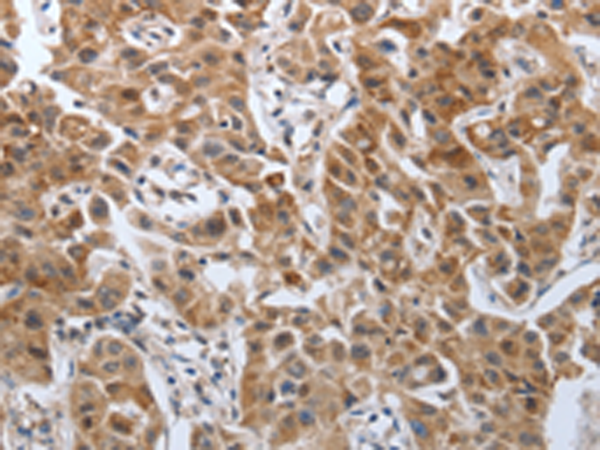

分类: 科研抗体货号: P11313别名: PDGF1, PDGF-A应用: IHC反应种属: Human, Mouse, Rat